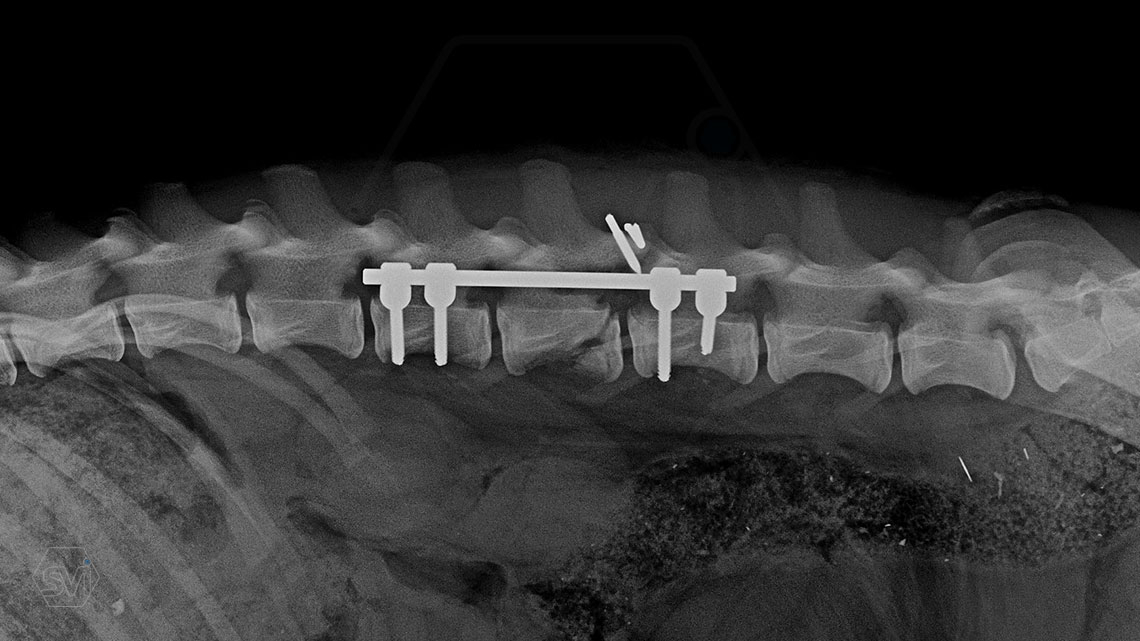

The best method to stabilize the spine is our patented SOP-LC system.

A gerinc stabilizálására a legjobb módszer a szabadalmaztatott SOP-LC rendszerünk.

Kutya neve: Benetton, az SOP-LC hatékonysága és stabilitása magáért beszél, a gyógyulás alatt a gerinc folyamatos terhelés alatt volt, és a fémek nem mozdultak el. A kutya szerencsére neurológiailag i felépült! Tehát van esély a gerinctörések esetén is a gyógyulásra...